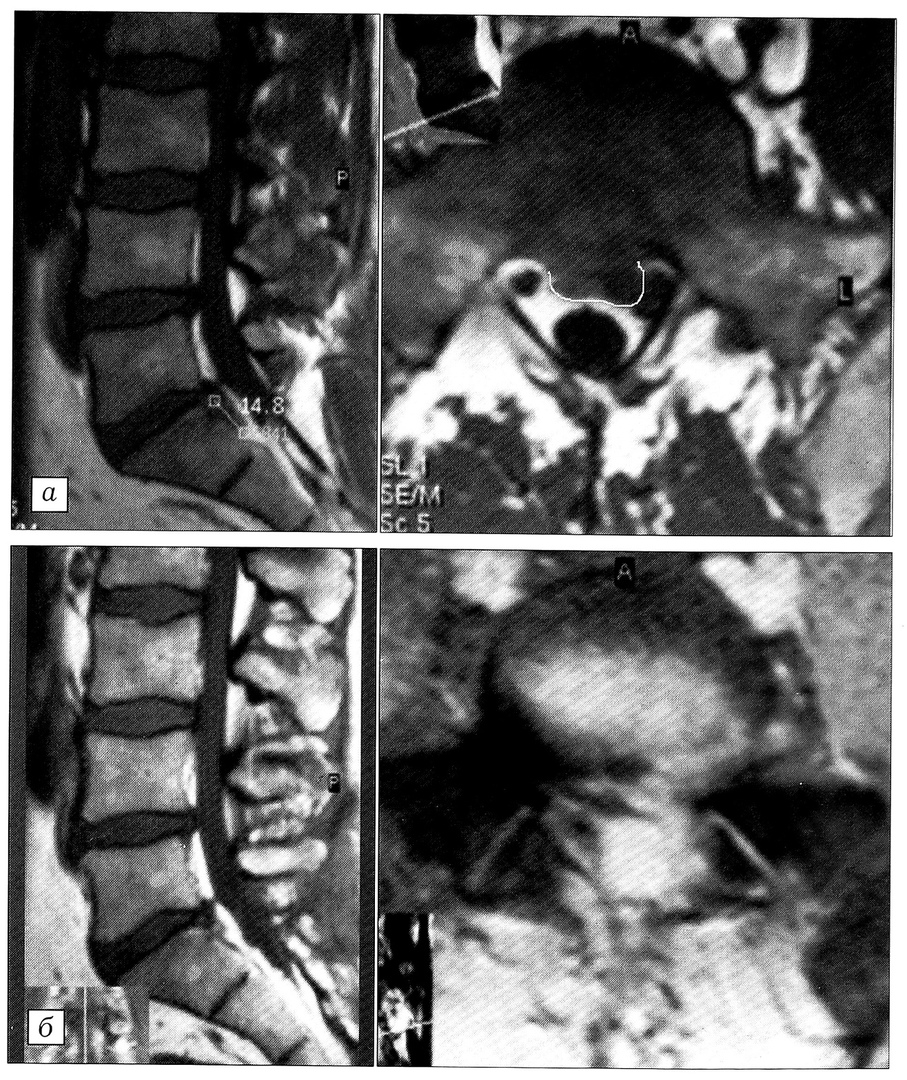

Рис. 1. МРТ поясничного отдела позвоночника больного Г. в сагиттальной и аксиальной проекциях: a — до операции, б — после операции.

Больной Г., 44 лет, госпитализирован в отделение неврологии МЦ с жалобами на резкие боли в пояснично-крестцовом отделе позвоночника с иррадиацией по задненаружной поверхности левого бедра и голени, усиливающиеся при физической нагрузке (оценка по карте болевого аудита 45 баллов). Боли в позвоночнике беспокоят около года, к врачу не обращался. Настоящее обострение наступило 21.08.99 после физической нагрузки. Обратился в поликлинику МЦ 23.08.99, в экстренном порядке госпитализирован. В приемном отделении произведены рентгенография поясничного отдела позвоночника, КТ сегментов L3-4, L4-5, L5-S1. Поставлен диагноз: дискоз L4-5, L5-S1; протрузия диска L4-5, левосторонний срединно-боковой пролапс (?) диска L5-S1; левосторонний компрессионно-корешковый (S1) синдром; мышечно-тонический синдром поясничных мышц. Больной записан на МРТ позвоночника, начата консервативная терапия острой фазы заболевания.

26.08.99 вечером состояние пациента ухудшилось: усилились боли в позвоночнике и левой ноге (по карте болевого аудита 76 баллов), остро развилась клиника синдрома миелорадикулоишемии («конского хвоста») — задержка мочеиспускания, гипестезия в области промежности и зоне корешковой иннервации S1 слева, парез левой стопы, угнетение коленного и-ахиллова рефлексов слева, симптом Бабинского с обеих сторон. В экстренном порядке произведена МРТ поясничного отдела. Выявлены признаки дегенерации межпозвонковых дисков на уровне L4-S1, циркулярная протрузия диска L4-5, пролапс диска L5-S1 с признаками секвестрации (рис. 1, а).

Утром 27.08.99 выполнена операция — микродискэктомия L5-S1 слева с удалением секвестров диска, сдавливавших твердую мозговую оболочку и нерв. Через сутки после операции боли в позвоночнике и ноге значительно уменьшились (по карте болевого аудита 19 баллов), восстановилась функция мочевого пузыря, на 2-е сутки больному разрешено ходить в ортопедическом поясе. К моменту выписки на восстановительное лечение (08.09.99) боли практически полностью исчезли (по карте болевого аудита 9 баллов), регрессировал парез мышц левой голени. Через 2 мес пациент приступил к работе по прежней профессии без ограничений физической нагрузки. Поданным МРТ, компрессия невральных структур в области операции устранена (рис. 1, б).